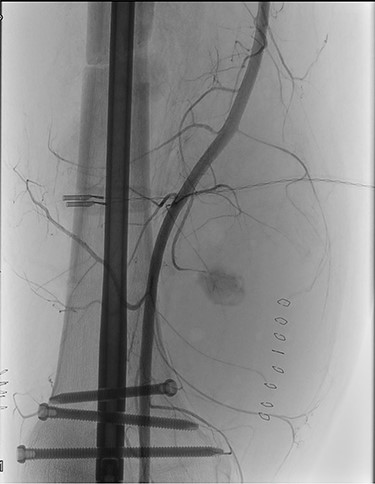

An emergency vascular surgery consultation was required. Upon our arrival, the foot was hypothermic and pale, with pain and paraesthesia. At the angiography, near occlusion of the SFA at its middle third was found, with concomitant occlusion of the popliteal artery and of the leg arteries (Fig. 2).

ONYX 34 residuals in the distal popliteal artery and in the tibioperoneal trunk obstructing blood-flow in the right lower limb.